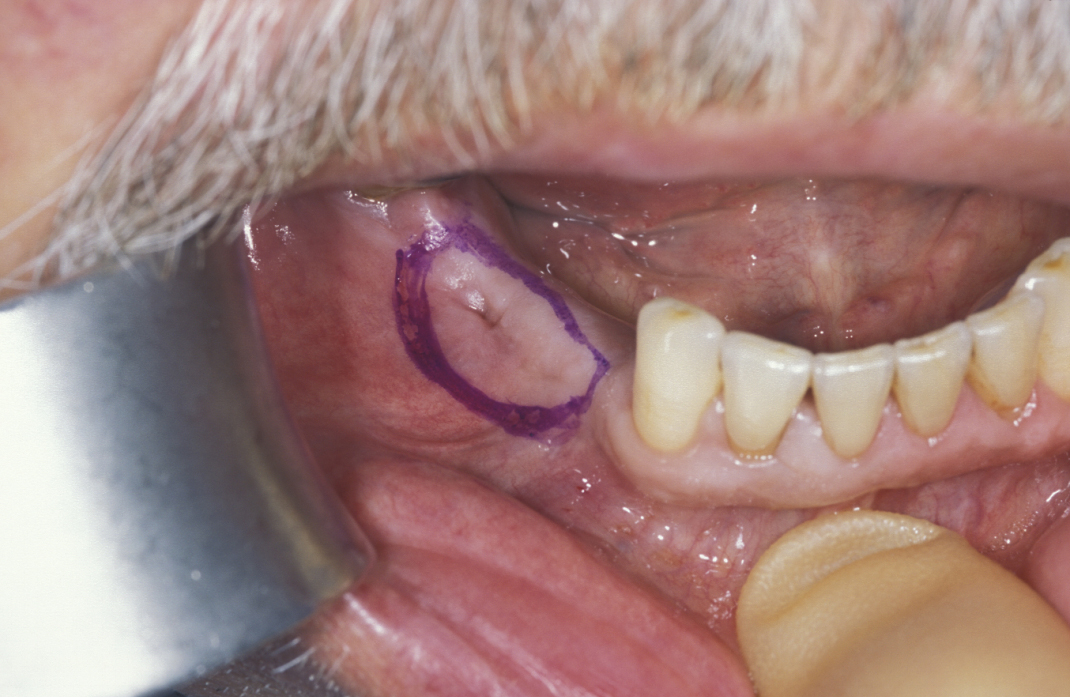

Figure 7: Marsupialization of a cyst that is in contact with the overlying mucosa. The area of mucosa to be excised is marked (in purple).

Figure 8: The cyst lining is retained and in continuity with oral epithelium externalizing the cyst.